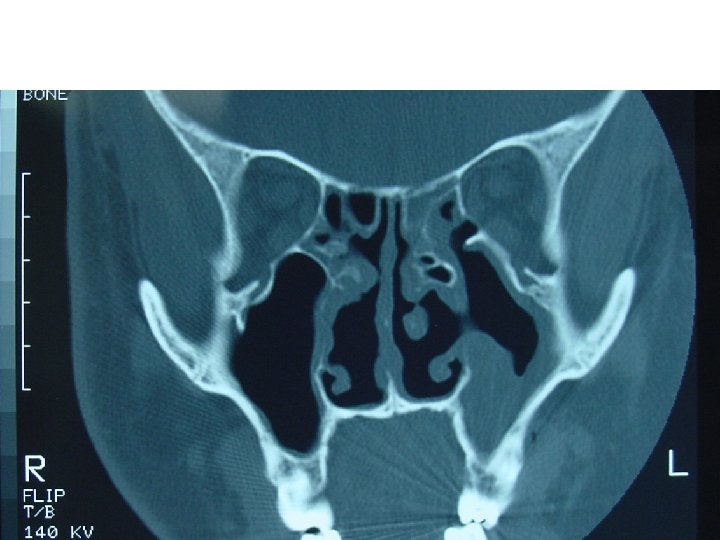

Ethmoid Sinusitis

Coronal computed tomographic scan showing ethmoidal polyps. Ethmoid opacity is total as a result of nasal polyps, with a secondary fluid level in the left maxillary antrum.